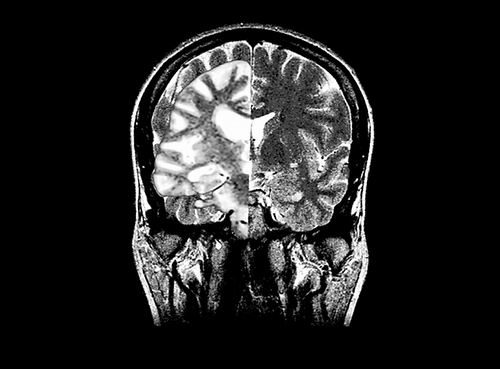

图片来源:Medical Body Scans/Jessica Wilson/SPL